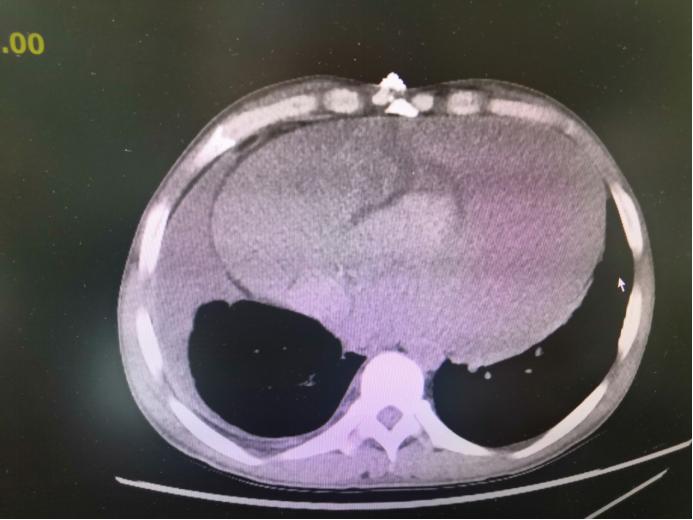

守得云开见月明,2个月前小凯终于等来合适肾源的消息。可就在小凯进行肾移植术术前评估时候,胸部CT检查提示心包大量积液。这种情况下如果冒险手术,心脏无法耐受,随时可能停跳。肾移植术不得不按下暂停键,这对小凯来说无疑是一个晴天霹雳。

CT下显示大量心包积液